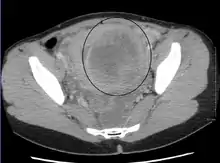

Diagnosis

Physical examination and ultrasound are sufficient for diagnosing uterine fibroids in the majority of patients. When ultrasound findings are inconclusive, magnetic resonance imaging (MRI) may be able to confirm the diagnosis of uterine fibroids in most cases. In addition, MRI can identify benign uterine fibroids with atypical imaging features and fibroids with variant growth patterns. MRI can also identify other uterine (e.g. adenomyosis, endometrial polyps, endometrial cancer) and extrauterine (e.g. benign and malignant ovarian tumors, endometriosis) disorders that may mimic the appearance of uterine fibroids and/or contribute to the patient's symptoms.[37] However, a small proportion of uterine fibroids can mimic other malignant uterine tumors (e.g. leiomyosarcoma) on all available imaging modalities (e.g. ultrasound, CT, MRI and PET-CT).[37]

Malignant tumors of the uterine wall (e.g. leiomyosarcoma) are very rare. Findings suggestive of a malignant uterine tumor rather than a benign fibroid include, fast or unexpected growth (particularly after menopause), interruption/effacement of the endometrial stripe, lymph node enlargement, invasion of adjacent organs and metastases to distant organs (e.g. lung). MRI findings suggestive of a malignancy include nodular/ill-circumscribed tumor margins, intermediate/high T2-weighted signal intensity of the solid tumor components, regions with high signal T1-weighted sequences in keeping with subacute hemorrhage, fine/wispy enhancement of the solid parts of the tumor, and restricted diffusion on diffusion-weighted imaging (DWI).[37] A biopsy is rarely performed and if performed, is rarely diagnostic. Should there be an uncertain diagnosis after ultrasounds and MRI imaging, surgery is generally indicated.[38]